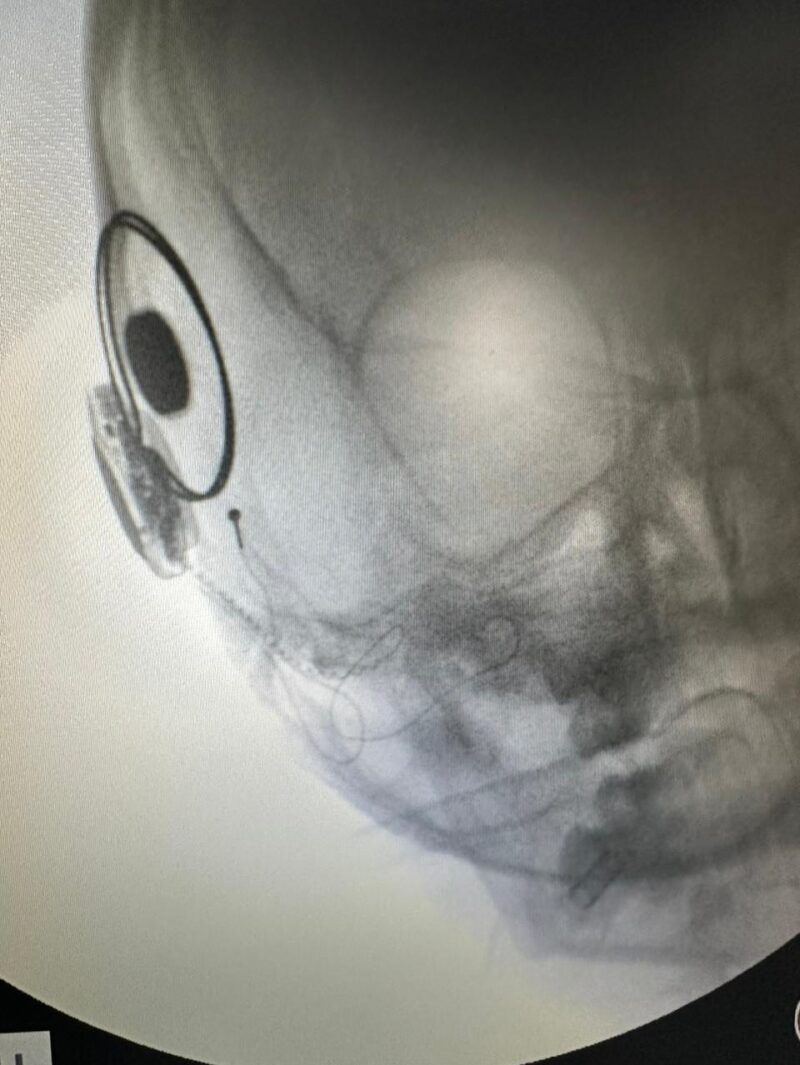

La cirugía de Sofía se realizó el 7 de agosto, tuvo una duración aproximada de dos horas y la niña recibió el alta a los dos días, lo que, dada la complejidad de la intervención, fue considerada un «alta inmediata».